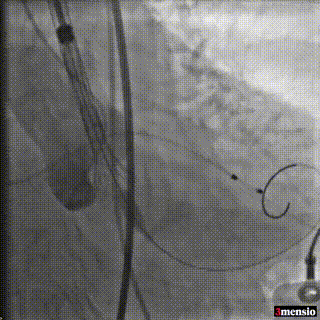

释放初始位提高2mm左右释放,造影观察位置

释放到2/3工作位,观察是否会位移

瓣膜锚定稳固,在起搏状态下缓慢脱钩,同时轻顶输送器卸张力

术后超声评估:

超声结合长轴短轴评估,无明显反流,瓣膜工作状态良好